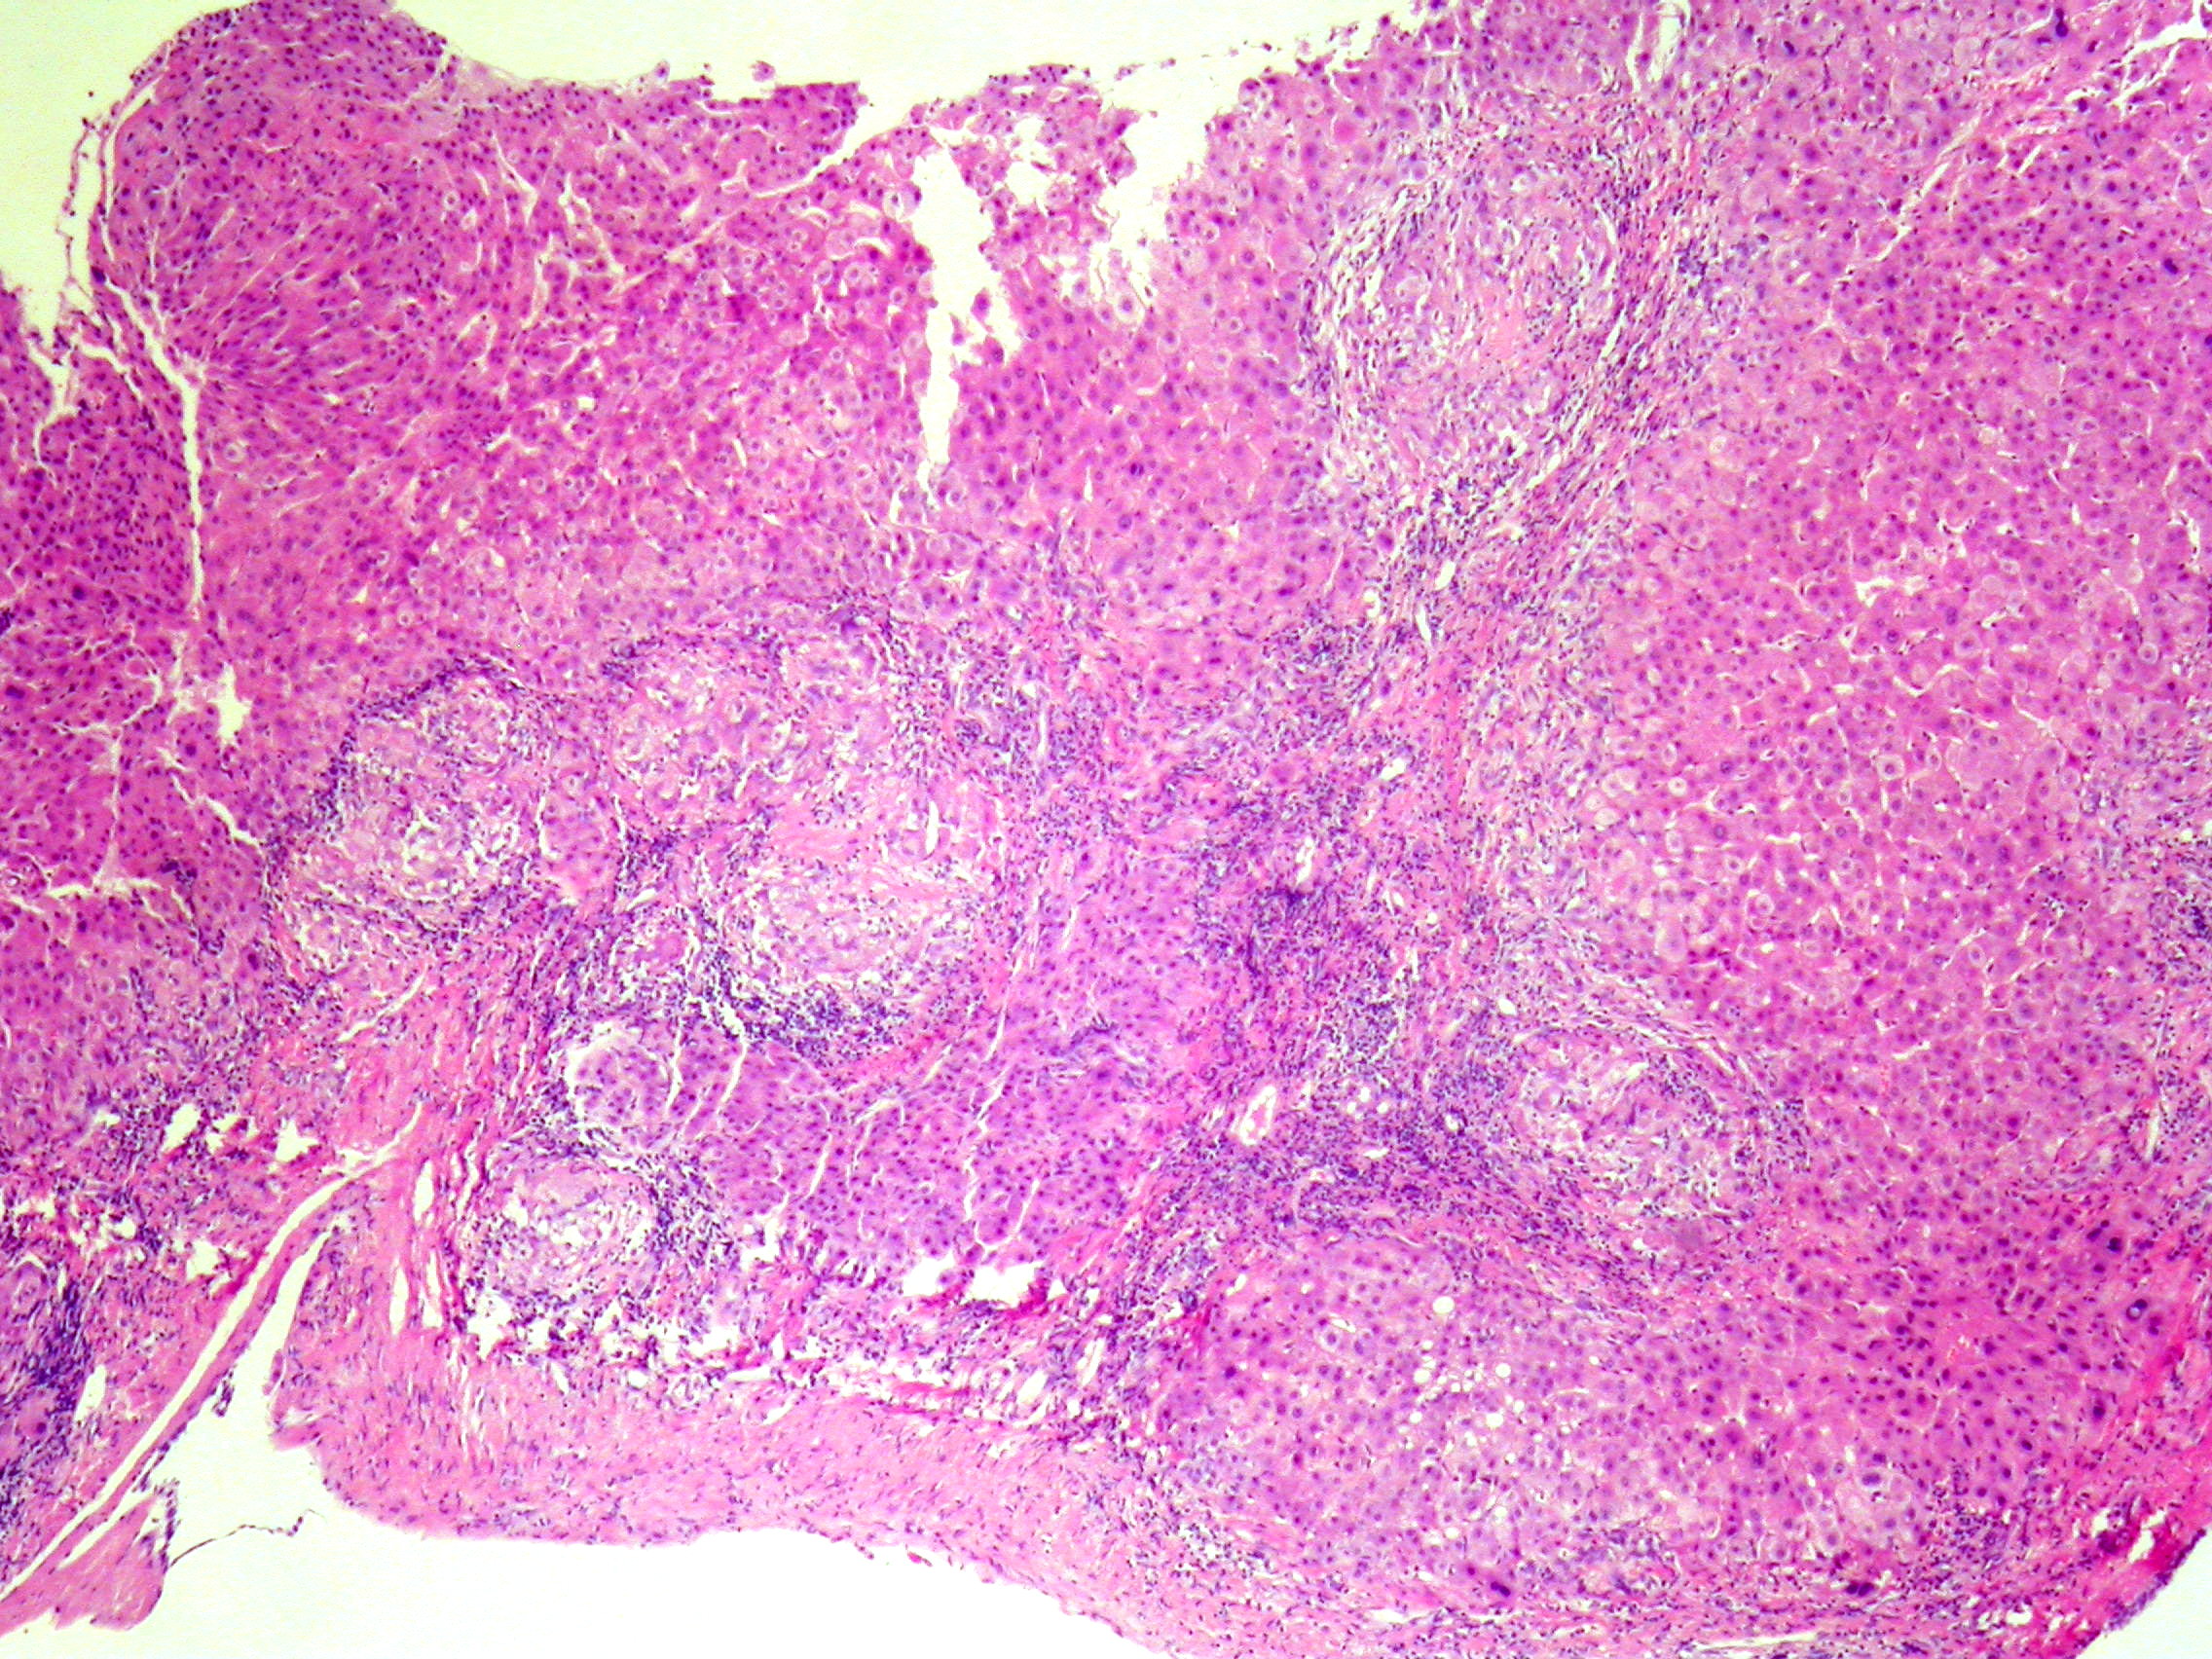

Boricic, Ivan